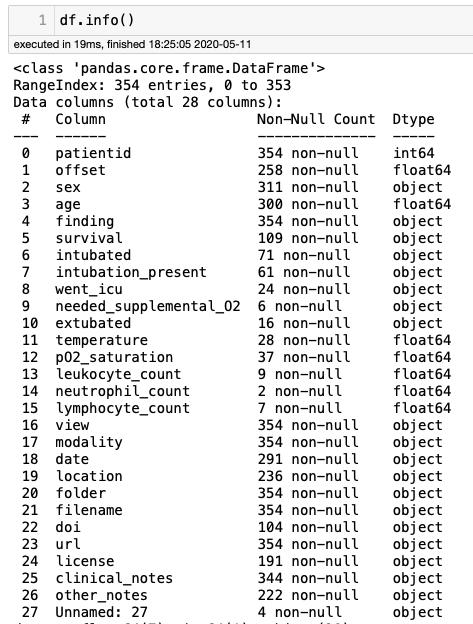

metadata.csv文件将提供有关/images/文件中的图像信息。

csvPath = os.path.sep.join([input_dataset_path, “metadata.csv”])df = pd.read_csv(csvPath)df.shape

metadat.csv文件有354行28列,这意味着在subdirectory /notebooks中有354个X光图像。让我们分析它的一些列,了解这些图像的更多细节。

通过df.modality,共有310张X光图像和44张CT图像。CT图像我们丢弃。

COVID-19 235Streptococcus 17SARS 16Pneumocystis 15COVID-19, ARDS 12E.Coli 4ARDS 4No Finding 2Chlamydophila 2Legionella 2Klebsiella 1

从可视化角度看,COVID-19的235张确认图像,我们有:

PA 142AP 39AP Supine 33L 20AP semi erect 1

如引言中所述,只有142张PA型图像(后-前)用于模型训练,因为它们是胸片中最常见的图像(最终数据框:xray_cv)。

“xray_cv.patiendid”列显示,这142张照片属于96个病人,这意味着在某些情况下,同一个病人拍摄了多张X光片。由于所有图像都用于训练(我们对图像的内容感兴趣),因此不考虑此信息。

根据xray_cv.date,2020年3月拍摄的最新照片有8张,这些图像被分离在一个列表中,从模型训练中删除,因此以后这将用作最终模型的验证。

imgs_march = [ ‘2966893D-5DDF-4B68–9E2B-4979D5956C8E.jpeg’, ‘6C94A287-C059–46A0–8600-AFB95F4727B7.jpeg’, ‘F2DE909F-E19C-4900–92F5–8F435B031AC6.jpeg’, ‘F4341CE7–73C9–45C6–99C8–8567A5484B63.jpeg’, ‘E63574A7–4188–4C8D-8D17–9D67A18A1AFA.jpeg’, ‘31BA3780–2323–493F-8AED-62081B9C383B.jpeg’, ‘7C69C012–7479–493F-8722-ABC29C60A2DD.jpeg’, ‘B2D20576–00B7–4519-A415–72DE29C90C34.jpeg’]

下一步将构建指向训练数据集(xray_cv_train)的数据框,该数据框应引用134个图像(来自Covid的所有输入图像,用于稍后验证的图像除外):

xray_cv_train = xray_cv[~xray_cv.filename.isin(imgs_march)]xray_cv_train.reset_index(drop=True, inplace=True)

而最终的验证集(xray_cv_val )有8个图像:

xray_cv_val = xray_cv[xray_cv.filename.isin(imgs_march)]xray_cv_val.reset_index(drop=True, inplace=True)

下面的图片显示了在这个步骤结束时应该如何配置文件夹(无论如何在我的Mac上),此外红色标记的数字显示文件夹中包含的x光图像的相应数量。